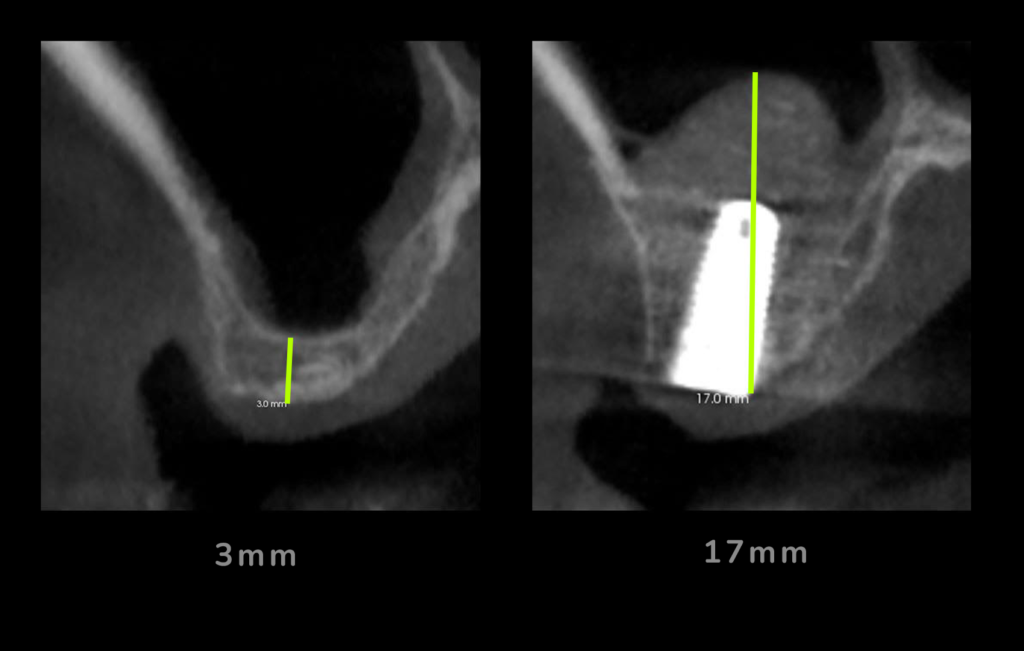

Este tipo de implantes se usan en aquellos casos en los que el paciente sufre una pérdida de hueso considerable. Gracias a los avances en la implantología dental, los implantes estrechos y los implantes cortos se han convertido en un tratamiento habitual en la práctica diaria obteniendo tasas de éxito muy altas, por lo que en determinados casos es una opción de tratamiento a tener muy en cuenta, ya que podemos colocar implantes en pacientes que no tienen mucho hueso sin necesidad de tener que realizar injertos y procedimientos más invasivos.

La única manera de saberlo de forma exacta es a través de un especialista que evalúe tu estructura ósea mediante un examen clínico y una radiografía o tac 3D de tus maxilares con la que se determina si tienes suficiente hueso para un implante dental estándar o si requieres algún procedimiento de injerto de hueso.

El volumen de hueso necesario para un implante dental varía según cada caso. De forma general, decimos que hay poco hueso cuando el ancho o el alto del hueso no es suficiente para soportar y rodear de hueso un implante dental.